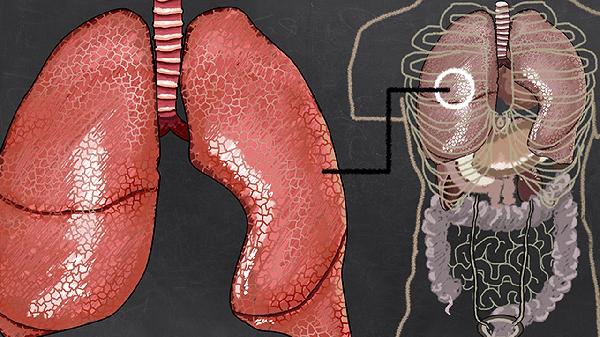

胸廓前后径增大呈桶状,肋间隙增宽,叩诊呈过清音。这是肺泡过度充气使胸廓持续处于吸气状态的表现,伴随呼吸时胸廓运动幅度减弱,听诊呼吸音普遍减弱。